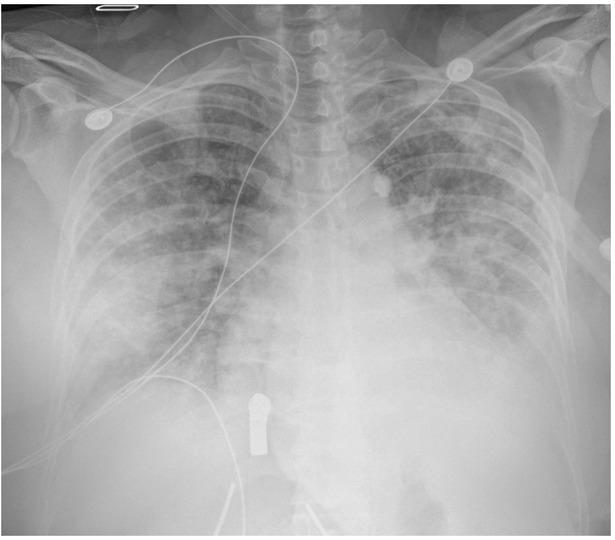

Fig. 1